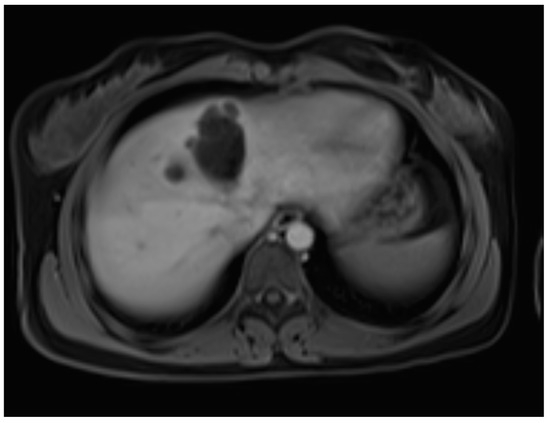

A liver MRI scan confirmed a cystic structure with multiple daughter cysts, hypointense on a T1-weighted image (T1WI), and hyperintense on a T2-weighted image (T2WI), with no solid components, no signs of membrane rupture, and a maximum diameter of 10 cm (craniocaudal) (Figure 1). Additionally, elevated signals on T2WI in the surrounding liver tissue were found. The T1 sequences did not reveal any contrast uptake after 5 (Figure 2), 10, or 20 (Figure 3) minutes post-injection. Furthermore, DWI/ADC mapping indicated a hydatid cyst. The DWI sequences included a trace DWI (Figure 4), an ADC map (Figure 5), and both at b800. Radiomics and AI tools were not involved. The trace DWI showed an area of hypointensity in the region of the cyst that was surrounded by a hypointense layer, depicting the cystic wall. The ADC map revealed hyperintensity within the area, in concordance with a typical depiction of cysts on an MRI scan.

Figure 2.

First MRI scan: Axial T1W MRI scan showing hypointense daughter cysts in liver segment IV with no contrast uptake after 5 min.

MR imaging clearly visualizes pericyst, matrix, and daughter cysts. The pericyst appears as a hypointense rim on both T1WI and T2WI due to its fibrous structure and the presence of calcifications. This is a specific feature of hydatid cysts, called the rim sign, mostly better visualized on T2WI [5]. The matrix represents hydatid-fluid-containing membranes of broken daughter vesicles, scolices, and hydatid sand [7]. The hydatid matrix appears hypointense on T1WI and significantly hyperintense on T2WI. However, the limitations of MRI scans are especially observed in stages CE4–CE5, as bigger calcifications are better observed on a CT scan. When daughter cysts are present, they are typically more hypointense than the matrix on T2WI, as observed in our case report [17] (Figure 1). If the membrane is separated, it can shift with movement, resembling a water lily floating on the surface of a pond, previously described as water-lily sign, which was seen in our case report as well [18] (Figure 8).